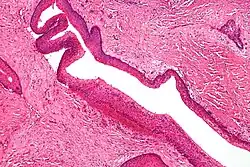

Familial adenomatous polyposis (FAP) is an autosomal dominant syndrome that greatly increases the risk of colorectal cancer. Around 1 in 8000 people will have this disease and it has approximately 100% penetrance. An individual with this disease will have hundreds to thousands of benign adenomas throughout their colon, which will in most cases progress to cancer. Other tumors increased in frequency include; osteomas, adrenal adenomas and carcinomas, thyroid tumors and desmoid tumors. The cause of this disorder is a mutated APC gene, which is involved in β-catenin regulation. Faulty APC causes β-catenin to accumulate in cells and activate transcription factors involved in cell proliferation, migration, differentiation and apoptosis (programmed cell death).[17][18][19]